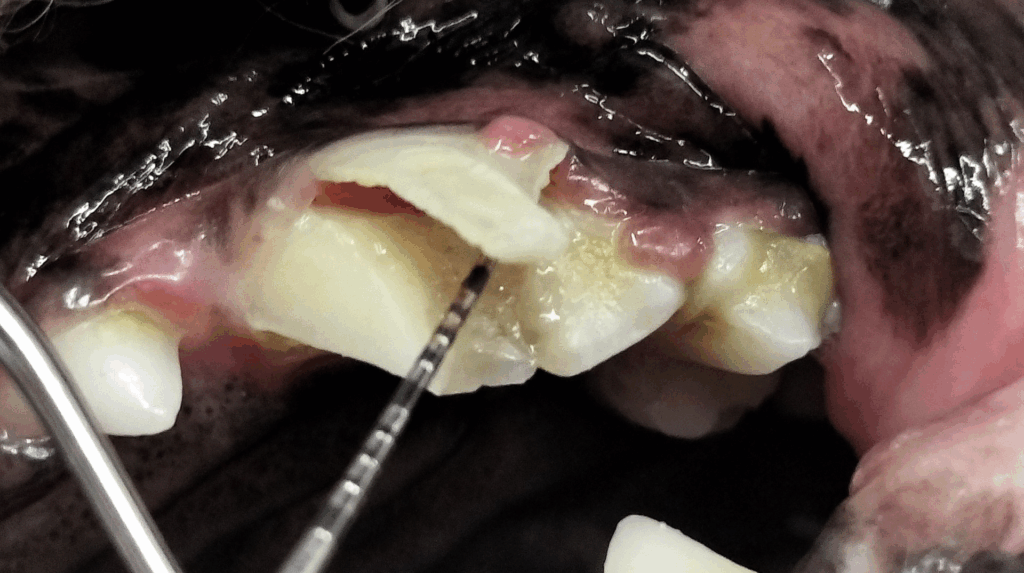

柴犬7才の避妊メス。トリミングサロンに行って、トリマーさんに歯が欠けて痛そうです、と指摘されてご来院頂きました。

写真をご覧いただくと、縦に歯が裂けているのがわかります。

お話を伺うと、おやつに鹿の角をあげていたそうです。

鹿の角のおやつは、犬用おやつとして売っていますが、注意が必要です。

ほとんどのワンちゃんで歯が欠けたり折れたりするのは、この奥歯が一番多いケースですね。

犬の場合、破折が最も多いのは「上顎の犬歯(大きなキバ)」と「上顎第4前臼歯(奥歯の中で最も大きい歯)」(症例写真📸)です。